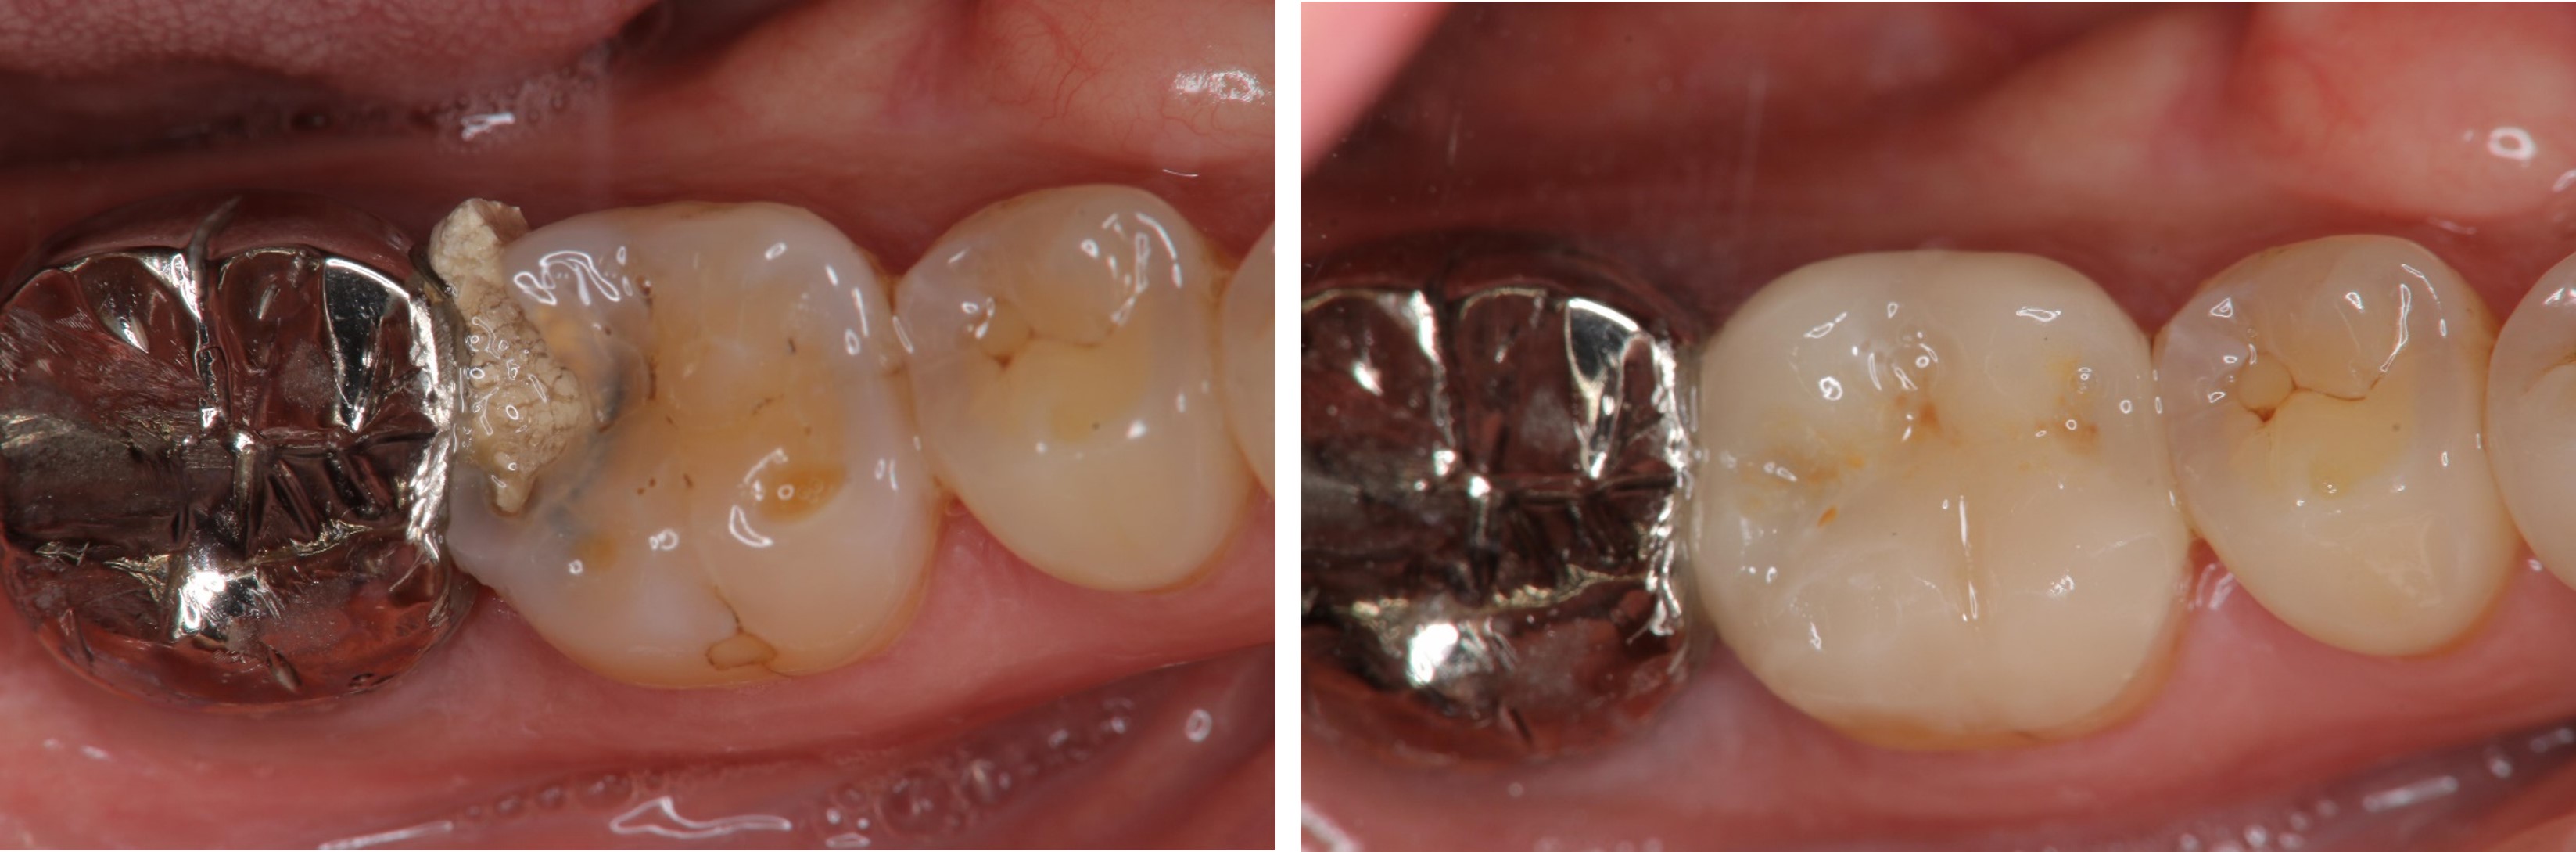

術前、術後比較

當蛀牙破壞程度大

陶瓷冠塊體是根據蛀牙的窩洞量身訂做,不管是顏色、精密度都是最佳的選擇,因此是非常美觀與持久的填補窩洞材料與技術